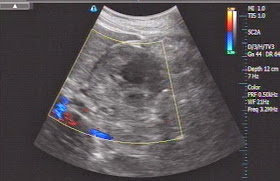

But ultrasound detected one round mass of 4 cm at the head of pancreas,

without dilated CBD or Wirsung duct. CDI no detection vascular intratumor and

echostructure was inhomogeneous (see 3 US pictures).